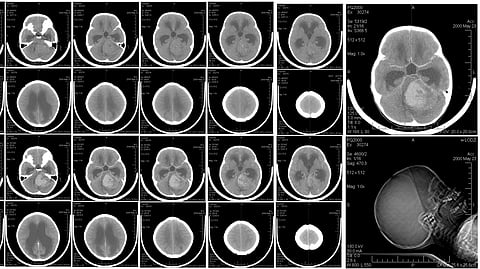

A collection of multiple MRI images displayed together, showcasing various scans and medical imaging results.

Medulloblastomas are one of the most common childhood brain cancers.Wikimedia Commons